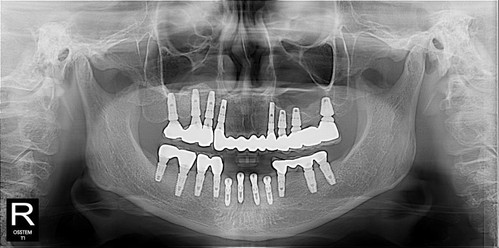

"그럼 나 저기 앞에 적혀있는 수면 마취 뭐 저런거 할 수 있나?"

네 그럼 그렇게 하시죠.

편안히 수술 받으셨으면 됐죠^^

이제 앞니 보철 할 때까지 기다리시기만하면 됩니다.~